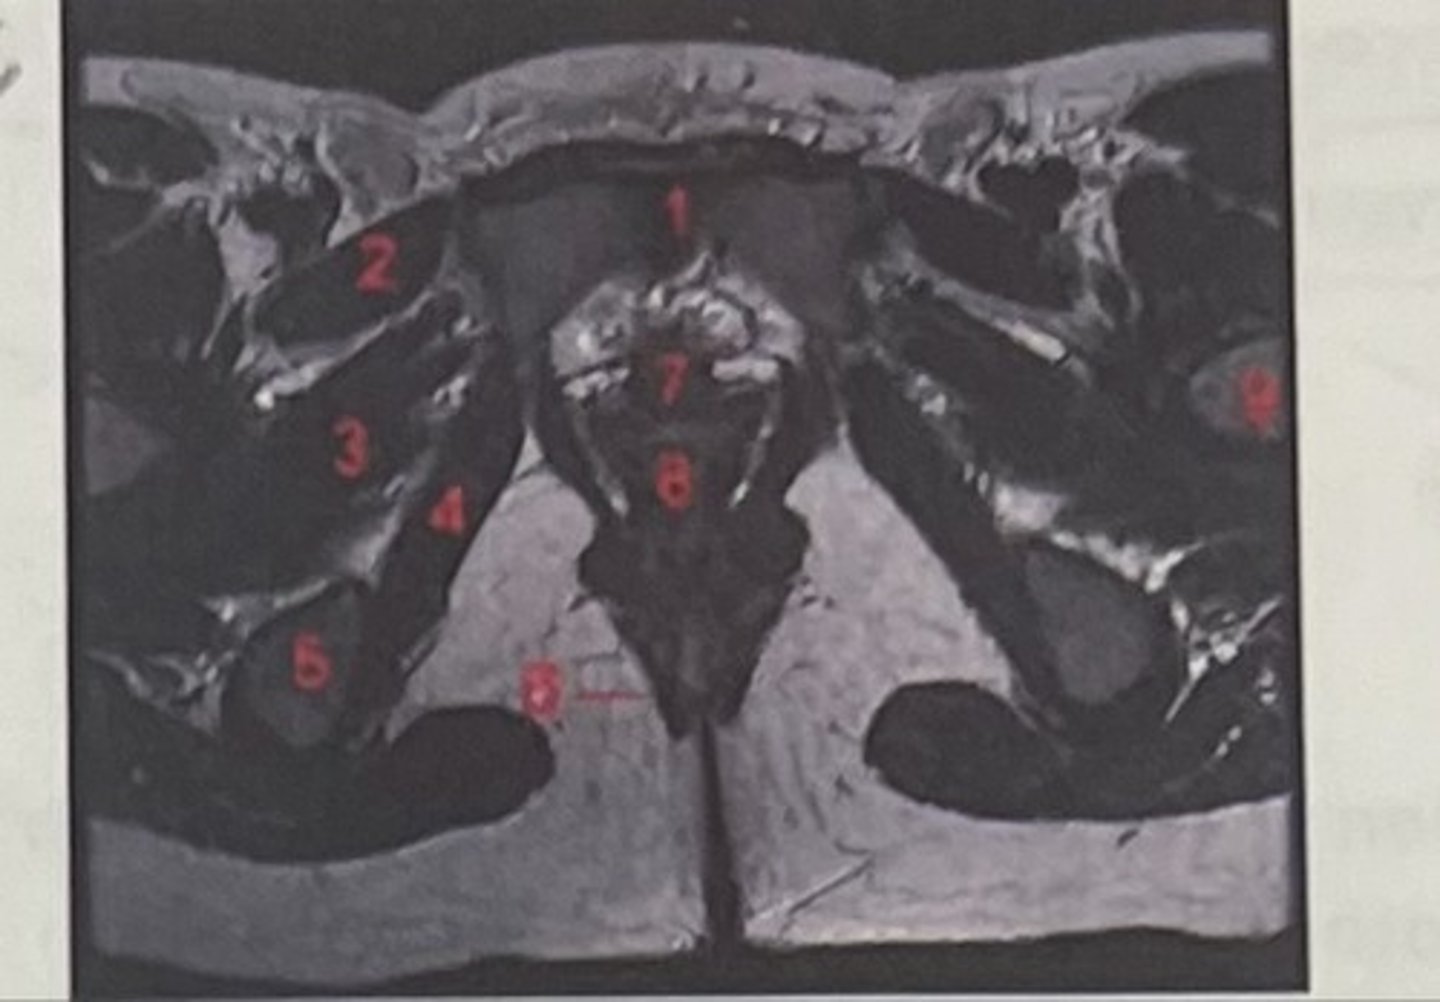

pubic symphysis

What is 1

Pectineus

What is 2

Obturator externus

What is 3

obturator internus

What is 4

ischial tuberosity

What is 5

external spincter

What is 6

Urethra

What is 7

Vagina

What is 8

Femoral nerve

What is 9